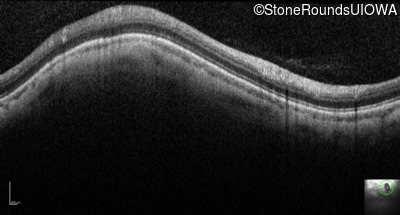

Optical Coherence Tomography - Left - 20/100

Exemplar